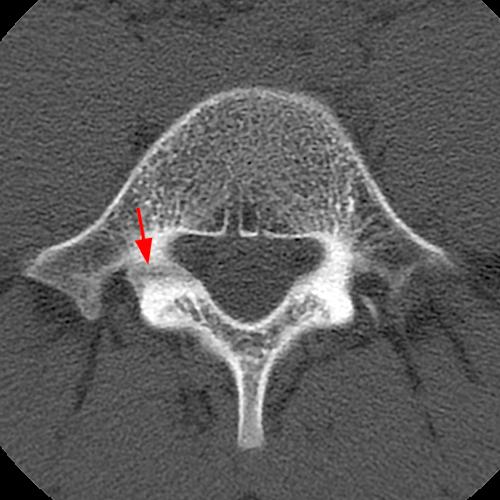

Case 1: T2-weighted axial (3A) and sagittal STIR (3B) sequences show marked cortical T2/STIR hyperintensity in the left pedicle of L5 surrounding a hypointense line (arrows) which begins at the inferior/medial margin of the pedicle and nearly completely traverses the pedicle.

Case 1: Acute left-sided pediculolysis